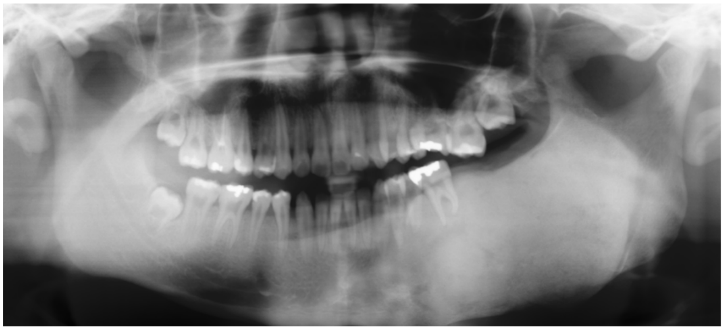

64.下圖所示之X光影像與何種拍攝方式所產生的影像最為接近?

(A)Water's view (B)Submental vertex view (C)Posterior-anterior view (D)Anterior-posterior view